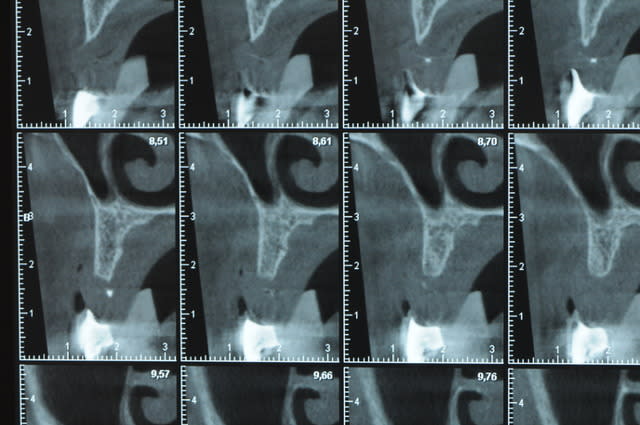

Une petite étude de ton cas D57

Les zones exploitables radiologiquement parlant:

Coupes implant

2,3 40100

4,96 35130 avec sinus lift mais difficile

5,25 35150

6,02 35130

6,78 35115 après réduction de hauteur de crête

7,26 35115 après réduction de hauteur de crête

8,51 35150

10,43 40115 ou 50115

11,10 40115

Ce qui nous fait 9 implants possible évidement avec un comblement de sinus on augmenterait encore les zones implantable mais ce n’est pas le but recherché, avec 8 (4+4) il doit être possible de faire une belle barre support de complet